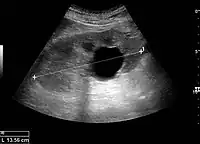

Cystic renal masses

Masses are seen as a distortion of the normal renal architecture. Most renal masses are simple cortical renal cysts with a round appearance and a smooth thin capsule encompassing anechoic fluid. The incidence increases with age, as at least 50% of people above the age of 50 have a simple cyst in one of the kidneys. Cysts cause posterior enhancement as a consequence of reduced attenuation of the ultrasound within the cyst fluid (Figure 5). The simple cyst is a benign lesion, which does not require further evaluation.[1]

Complex cysts can have membranes dividing the fluid-filled center with internal echoes, calcifications or irregular thickened walls. The complex cyst can be further evaluated with Doppler US, and for Bosniak classification and follow-up of complex cysts, either contrast-enhanced ultrasound (CEUS) or contrast CT is used (Figure 6). The Bosniak classification is divided into four groups going from I, corresponding to a simple cyst, to IV, corresponding to a cyst with solid parts and an 85–100% risk of malignancy.[1] In polycystic kidney disease, multiple cysts of varying size in close contact with each other are seen filling virtually the entire renal region. In advanced stages of this disease, the kidneys are enlarged with a lack of corticomedullary differentiation (Figure 7).[1]

Figure 5. Simple renal cyst with posterior enhancement in an adult kidney. Measurement of kidney length on the US image is illustrated by '+' and a dashed line.[1]

Figure 6. Complex cyst with thickened walls and membranes in the lower pole of an adult kidney. Measurements of kidney length and the complex cyst on the US image are illustrated by '+' and dashed lines.[1]